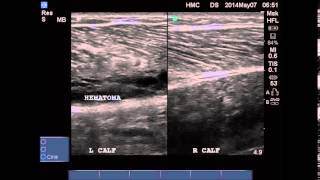

• Emergency Ultrasound Case: Tennis leg

Middle aged gentleman with left calf pain, swelling and bruising while playing basketball.